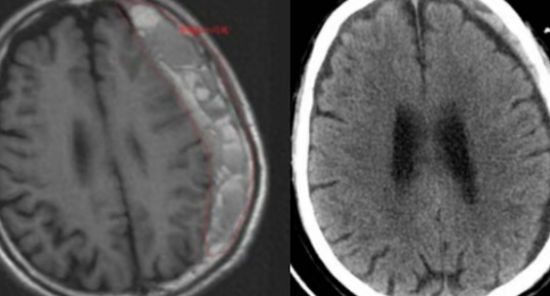

老年人摔倒 慢性硬膜下血肿 颅内出血